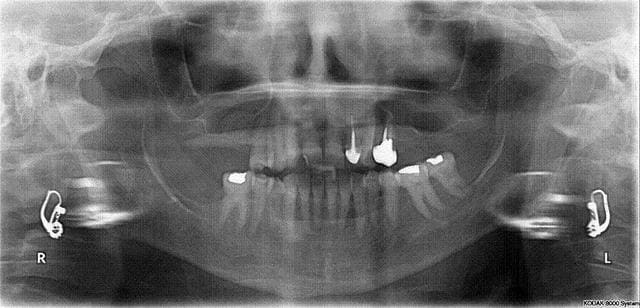

voila la pano!!!

Surcharge occlusale évidente sur les dents maxillaires, viens nous voir à Nancy le 30 juin... Possible aussi en petit comité le 13 juillet à Corte

1. Aucun renseignement sur la DV par la pano.